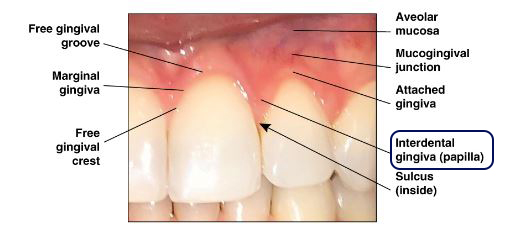

정말

예쁜 치아와 잇몸은

Papilla gingiva라 부르는 치간 유두가 중요합니다.

브릿지 는

길게 이어진 형태의 보철로

치아 사이에 있는 치간 유두를 재현하기 어렵습니다.

그렇지만

임플란트 수술을 통해서

앞서 말한 부위를 살려볼 수 있습니다.

앞서 말한 Papilla gingiva를 살리기 위해

개수별로 심기로 했습니다.

Papilla gingiva= 치간 유두를 살렸던 게

신의 한 수였던 것 같습니다.